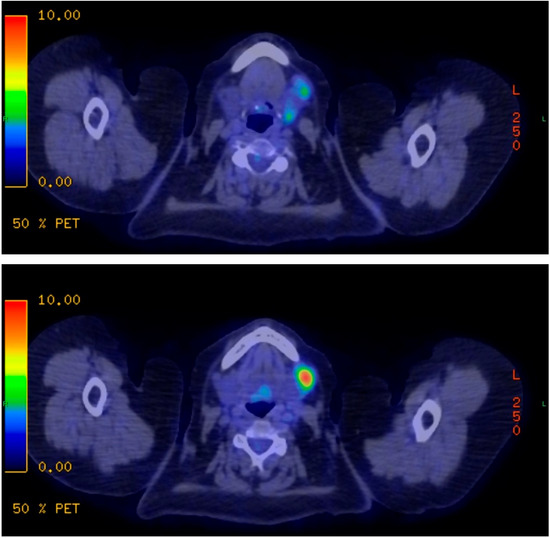

Due to the unsure histological results an excision of the cervical lymph nodes was recommended. During the examination at Semmelweis University’s Department of Otorhinolaryngology and Head and Neck Surgery, three pathological lymph nodes were noted in the left submandibular region. No other abnormalities were detected. A PET-CT scan was conducted on November 18, 2021, which revealed FDG accumulation in three lymph nodes on the left submandibular, upper jugular, and mid-jugular lymph nodes, regions I/b, II/a, and III. The lymph nodes had a diameter of 1.5 cm and variable FDG accumulation can be observed, with a maximum SUV (standardised uptake value) of 12.4 in the lymph node located ventrolateral to the submandibular gland. No signs of malignancy were detected in other areas (Figure 1).

Figure 1. PET-CT examination pictures. The scans represent lymph nodes around the left submandibular salivary gland with varying levels of FDG accumulation. FDG = fluorodeoxyglucose.